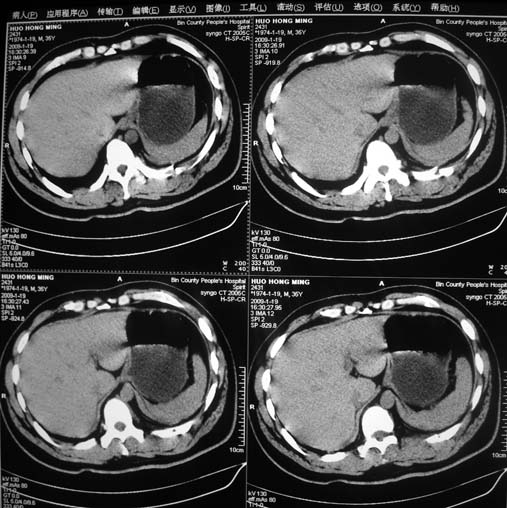

以下是引用余辉在2009-1-20 8:22:00的发言:[br]右侧肾上腺明显增大、边缘不光整,肯定有问题,结合患者病史考虑肾上腺挫伤、伴血肿形成。[br]另左肾后唇包膜下方可见局限性新月形高密度影,考虑肾包膜下出血[br]余同意楼上,建议增强排除脾破列

以下是引用随光逐影在2009-1-20 8:21:00的发言:[br]1)左侧多发肋骨及部分腰椎左侧横突骨折。2)左侧肾旁后间隙及同侧胸腔积血。3)左侧腰大肌肿胀。